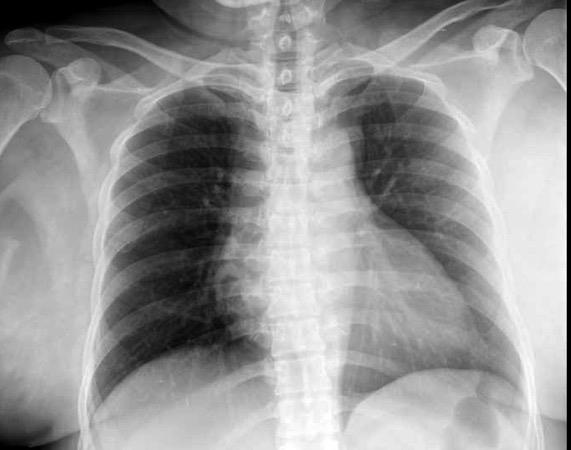

Masa axilar izquierda y derrame pleural derecho. Implantes pleurales, paraespinales . Ganglios en mamaria interna. Linfoma B difuso

Jaffe ES. Diagnosis and Classification of Lymphoma: Impact of Technical Advances.

2005. Masa pulmonar.